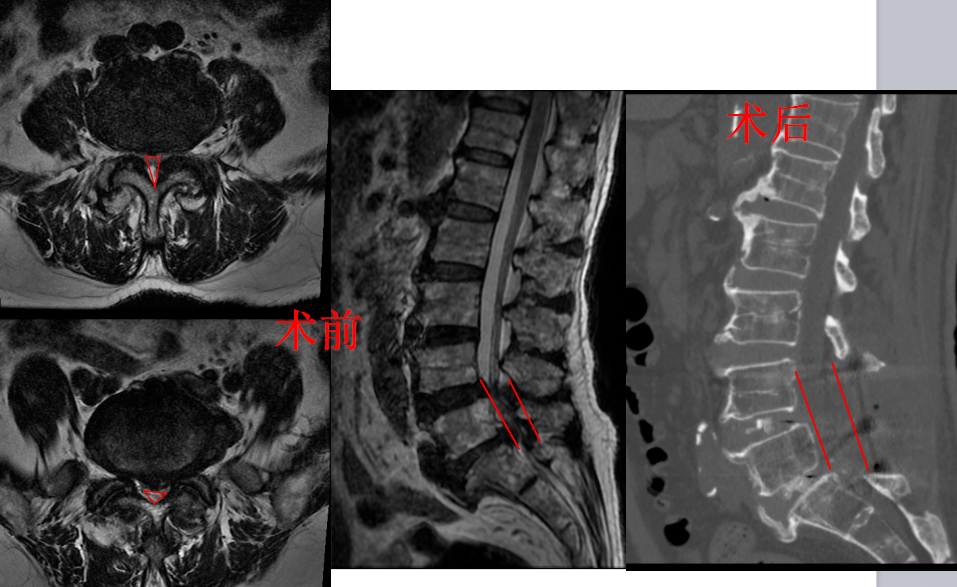

住院后,骨四科(脊柱外科)主任、主任医师姜树东带领全科医师讨论李大爷的病情,考虑李大爷自身疾病特点,双节段重度腰椎管狭窄、腰椎间盘突出,已经超出微创所能解决的范畴,具备开放手术指征。完善相关术前检查后及手术准备后,刘正详细与家属及本人交代手术情况及风险,家属及本人认同手术风险、同意手术。

住院第3天,由姜树东主刀,刘正和骨四科(脊柱外科)医师梁得华协助,共同为李大爷进行了手术。手术中,姜树东利用骨科机器人精确定位、超声骨刀削骨如泥,让手术更佳得心应手。术中医生发现,李大爷不光腰椎椎管狭窄、脊髓神经压迫严重,连后方椎管外也增生了厚厚的一层骨赘,最厚处达1cm,这给手术带来了挑战,所幸姜树东经验丰富、技艺精湛,刘正、梁得华配合得当,对李大爷的受压脊髓、神经进行了彻底减压,手术顺利。术后李大爷平安回到病房。